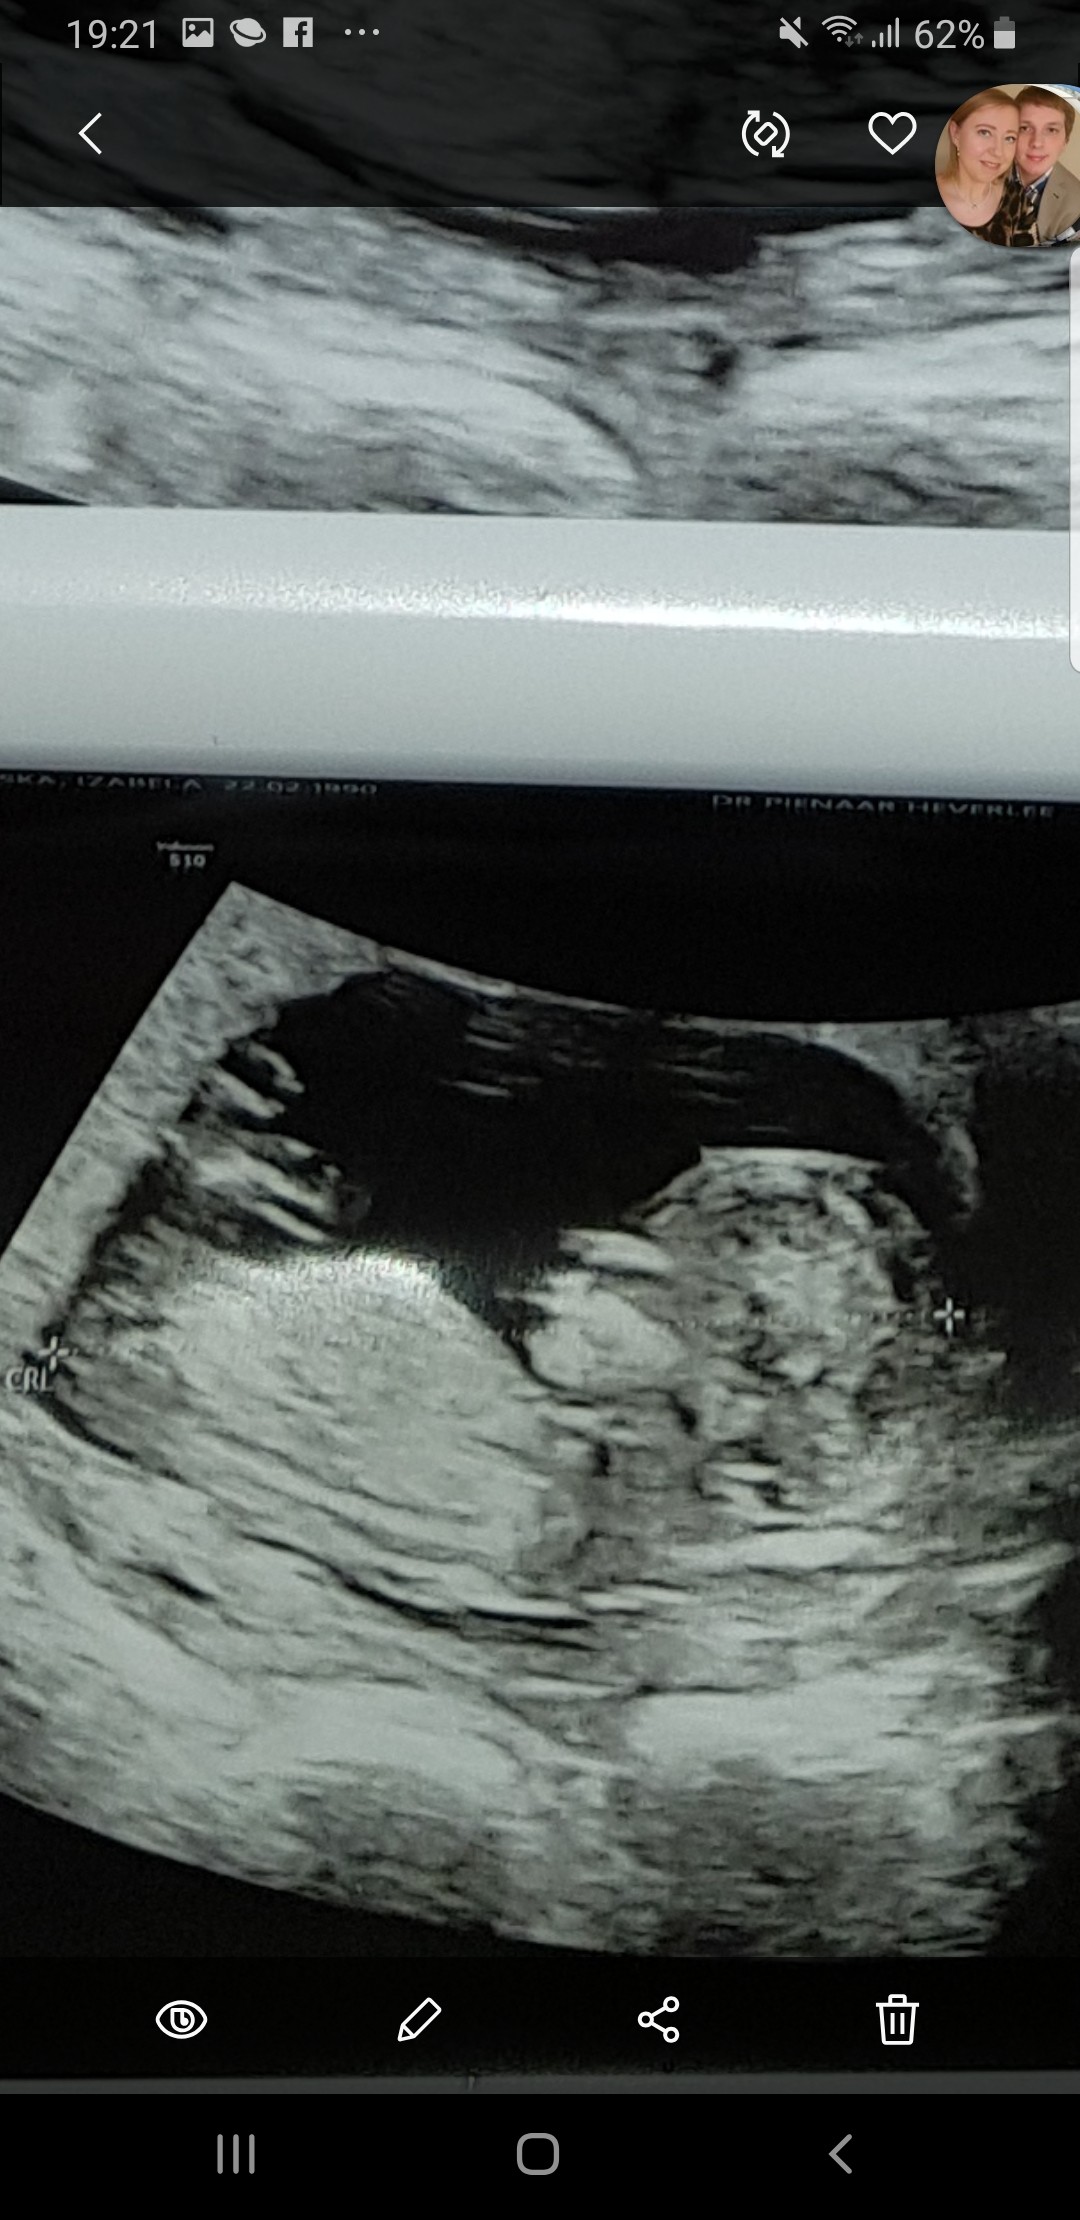

Plec z usg

Zdjecie w zalaczniku. Usg 13sty tydzien. Na moje nie widac tu zadnego wyrostka- jak to mowliwe???Czy w takim razie to dziewczynka? Lekarz sie nic nie chcial wpowiedziec :( Pomozcie dziewczyny specjalistki :*

Na szczescie musze tylko do wtorku czekac na wynik badania NIPT, wiec tylko tydzien od tego usg, ale i tak juz bym chciala wiedziec :P Czas sie jakby zatrzymal ha ha ha Wiem, straszna jestem :-) I jak neta i fora przegladam to juz te wyrostki widac i to nawet dokladnie w takim wieku ciazy.